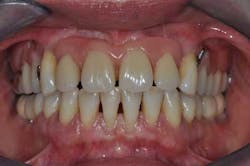

Fig. 2: Anterior teeth relationships prior to treatment

A 40-year-old woman, with no medical history except that she is a smoker (five cigarettes a day), is visiting us for an oral rehabilitation. Her chief complaints are teeth mobility and an esthetic concern since her maxillary front teeth are moving forward. The patient also suffers from dental anxiety.